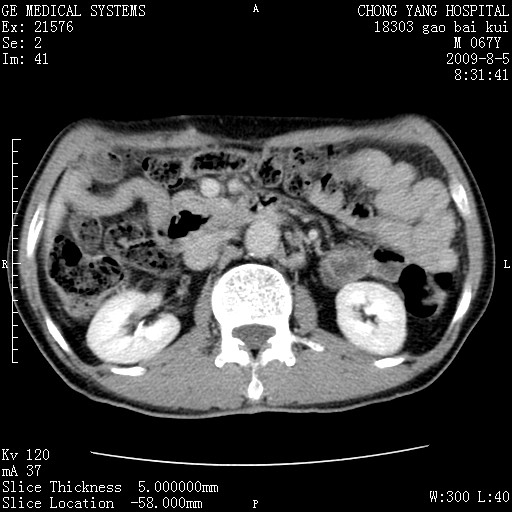

这个也过了,考虑胰腺钩突癌或壶腹癌,不除外胰管粘液乳头瘤伴胰管扩张,肝内胆管积气.

1)考虑胰头癌或壶腹癌并胰管扩张。2)肝外胆管扩张、积气,胆囊影未见;考虑术后改变。3)胃壁增厚?建议必要时行胃镜检查。

虑胰腺钩突癌或壶腹癌,不除外胰管粘液乳头瘤伴胰管扩张,肝内胆管积气.

考虑胰头癌并十二指肠受侵。